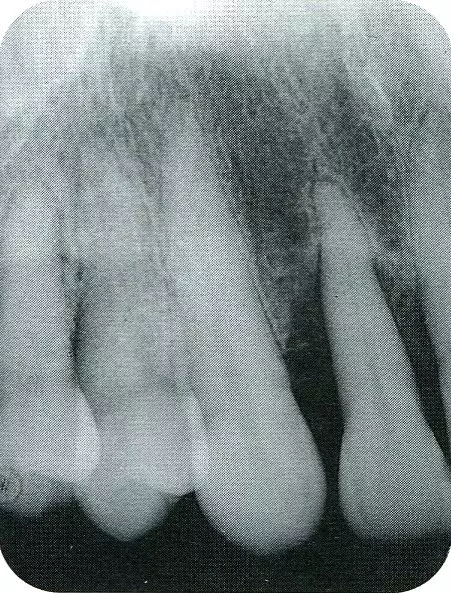

640.webp (1).jpg

▲圖7-2  術(shù)前x片。確認(rèn)存在垂直性深骨缺損。